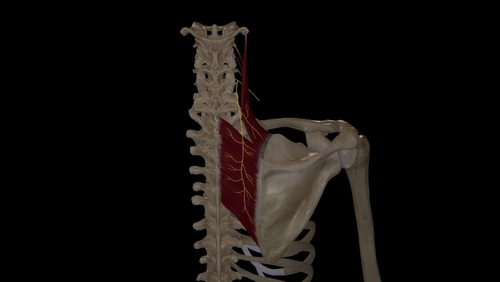

Rotator Cuff Pain: K Tape + Rehab Short-Term Effects

Nguyen, T. N. A., Nguyen, N. H., Vu, D. K., & Cu, L. T. N. (2025). Short-term effects ofKinesiotaping combined with a rehabilitation program for ...